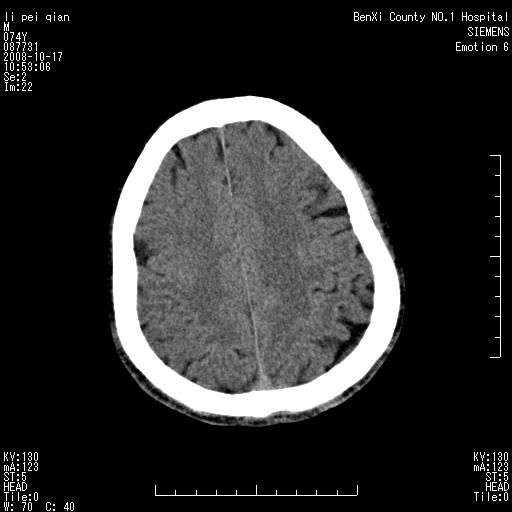

以下是引用影像孺子牛在2008-10-17 11:31:00的发言:[br]考虑:钙化。其一为病变密度特别高,其二如为出血其周围应有水肿带。